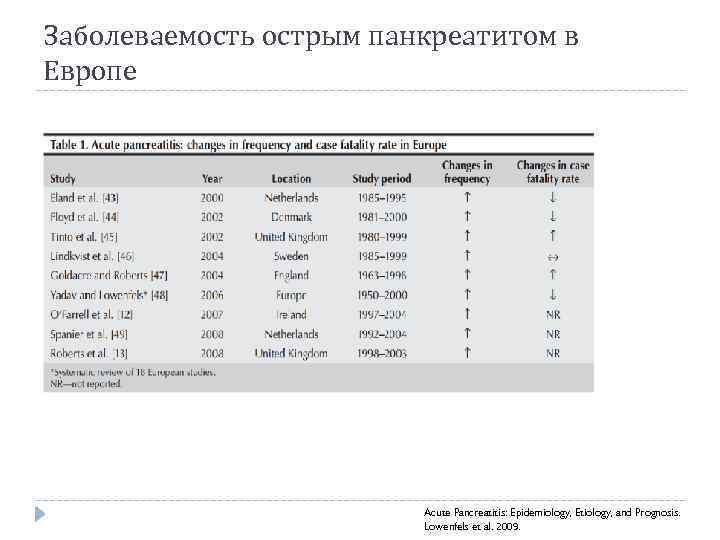

Заболеваемость острым панкреатитом в Европе Acute Pancreatitis: Epidemiology, Etiology, and Prognosis. Lowenfels et al. 2009.

Заболеваемость острым панкреатитом в Европе Acute Pancreatitis: Epidemiology, Etiology, and Prognosis. Lowenfels et al. 2009.